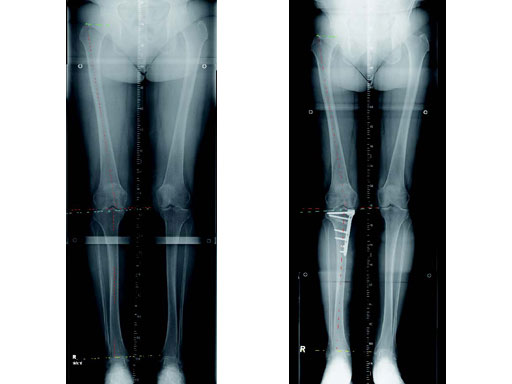

The correction is planned on a long-leg standing x-ray. After surgery, the mechanical axis should pass through a point 63% on the lateral side of the total width of the tibial plateau in the frontal plane. A transverse or slightly oblique incision is used to avoid damage to the saphenous nerve. The distal fibers of the medial collateral ligament are detached from the tibia. Under fluoroscopic control, two wires are placed in the proximal tibia marking the transverse osteotomy plane. The cut usually starts at the upper margin of the pes anserinus and ends at the tip of the fibula on the lateral side. The wires are placed exactly parallel to the tibial plateau thus taking into consideration the individual tibial slope of the patient. An incomplete cut of the posterior two-thirds of the proximal tibia is performed with an oscillating saw guided by the wires. Continuous irrigation avoids burn injury to the bone. A second osteotomy is now performed in the anterior third of the tibia in an angle of 100 ending above the patellar tendon insertion. A smaller saw blade is used and the complete anterior cortex is cut exactly in the frontal plane. The osteotomy is now gradually opened by inserting flat chisels or a spreader-chisel into the posterior osteotomy cleft. This process may take some minutes and can usually be completed without fracture of the lateral cortex. A bone spreader is now placed in the posteromedial edge of the tibia and the chisels are removed. The leg is extended and the correction is checked with the fluoroscope. A long metal rod is placed between center of the hip joint and center of the ankle joint. The projection of this rod should be at the planned point of correction on the tibial plateau lateral of the midline. Eccentric collapse of the medial joint space may cause accidental overcorrection. In this case pressure on the foot may simulate loading and body weight. The correction can be fine-tuned by opening or closing the spreader. The TomoFix Medial Tibia Plate is now placed in a subcutaneous pocket. The implant is precontoured and usually fits well to the bone surface. The distance holders avoid compression of the medial collateral ligament and the pes anserinus. Three proximal bolts are placed near the subchondral sclerosis zone. The position of the bolts is adapted to the anatomy of the proximal tibia giving optimum purchase for the bolts. An oblique lag screw is inserted distal to the osteotomy. This screw in the first combination hole allows careful compression of the lateral osteotomy hinge and pretensioning of the implant. A stab incision is created on the shaft and the implant is fixed monocortically with bolts. The lag screw and the distance holders are replaced by bolts. The medial collateral ligament is released longitudinally to reduce medial compartment pressure and the wound is closed in layers. An overflow drain may be used. Clinical and experimental work has proven that when this technique is closely followed, corrections up to and over 15 mm can be performed without bone grafting or use of bone substitutes.

A 68-year-old female.

Case provided by Alex Staubli, Luzern, CH